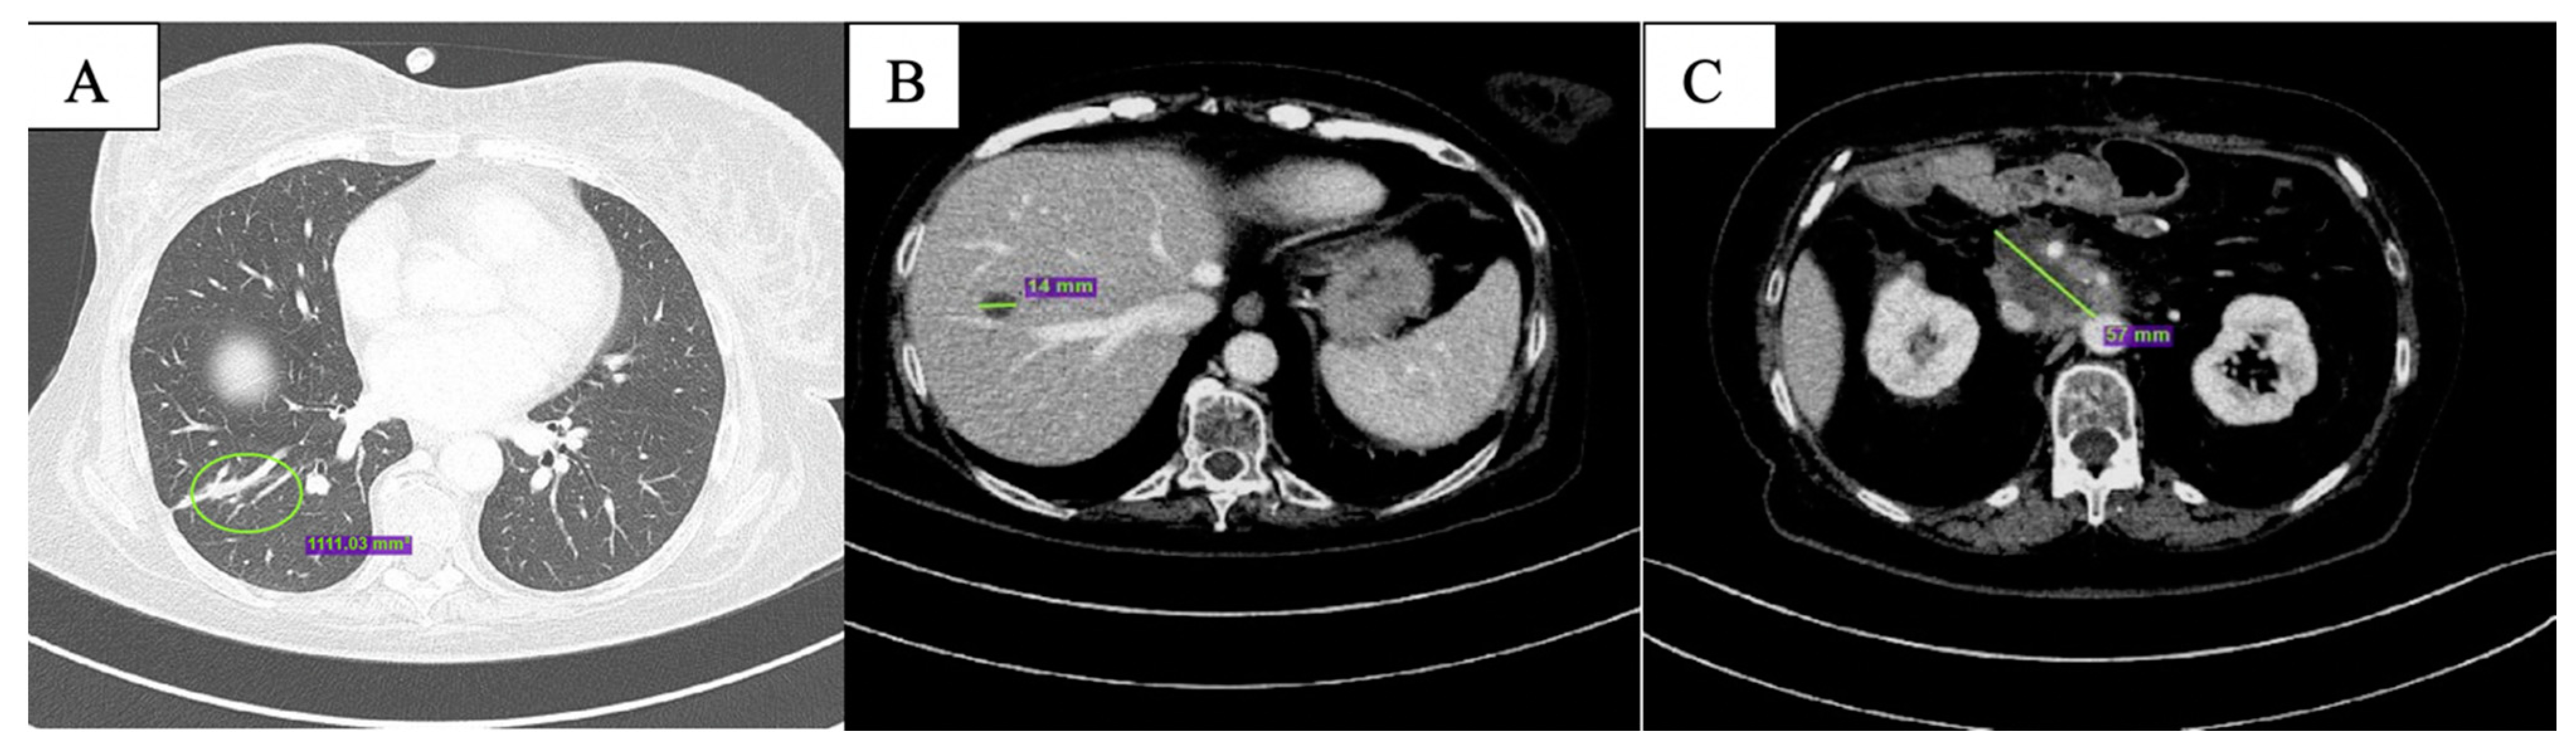

2. Case Description